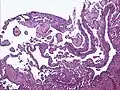

Low power photomicrograph of an endovascular papillary angioendothelioma showing papillae with hyalinized cores -

High power view showing a vascular tumor with cuboidal endothelium lining the vessels. Few entrapped seminiferous tubules are also noted (arrow). -

Characteristic budding, hobnail-like endothelial cells visible.